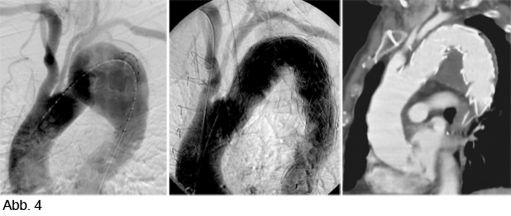

Die Abdomensonographie ist als Screeninguntersuchung und für eine routinemäßige Verlaufskontrolle bei Aneurysmen gut geeignet. Zur exakten Bestimmung der Größe und Morphologie wird jedoch eine Computertomographie (Abb. 1), in Ausnahmefällen eine Magnetresonanztomographie, durchgeführt.

Alternativ zur offenen chirurgischen Therapie eines Aortenaneurysmas besteht die Möglichkeit einer endovaskulären Aneurysmaausschaltung mittels eines Stentgrafts (gewebeummanteltes Metallgittergeflecht). Voraussetzung für die endovaskuläre Therapie ist jedoch eine anatomische Eignung, welche eine ausreichende Weite der Beckengefäße und nötige Verankerungszonen für den Stentgraft mit sich bringt. Die Stentgraft Implantation wird von Interventionellen Radiologen in Zusammenarbeit mit Anästhesist:innen und Gefäßchirurg:innen durchgeführt. Der Eingriff erfolgt unter Spinalanästhesie oder einer Allgemeinnarkose. Der Zugang zum Aneurysma wird üblicherweise durch einen kurzen Schnitt in der Leiste geschaffen. Zur Darstellung des Aneurysmas wird zuerst eine Angiographie der Bauchaorta durchgeführt (Abb.2). Folglich wird unter Röntgendurchleuchtung der Stentgraft über einen Führungsdraht in die Bauchaorta eingebracht und unterhalb der Nierenarterien verankert. Eine Kontrollangiographie nach Stentgraft-Implantation wird zum Nachweis eines guten Ausschlusses des Aneurysmas durchgeführt (Abb.3).

Bei elektiver chirurgischer Sanierung von Descendensaneurysmen wird die 30-Tages-Mortalität mit 5–13% angegeben. Weitere postoperative Komplikationen sind respiratorische Probleme, bis zu 33% neurologische Defizite und renale Insuffizienz bis zu 8%. Die endovaskuläre Stentgraft-Therapie hat deutlich geringere Mortalitäts- und Komplikationsraten und hat als Alternativmethode eine große Bedeutung in der Behandlung von Aneurysmen in der Aorta descendens und des Aortenbogens erlangt. Bei Beteiligung des Aortenbogens sind vorausgehende chirurgische Umbauten von Aortenbogenästen erforderlich, um eine Stentgraft Verankerung zu ermöglichen. Abbildung 4a zeigt ein Aneurysma mit Beteiligung des Aortenbogens und Abgang der linken Halsschlagader (Arteria carotis) und der linken armversorgenden Arterie (Arteria subclavia) in Nahebeziehung zum Aneurysma. Eine Stentgraft-Therapie kann in solchen Fällen nach Verlagerung (Transposition) der Arteria carotis und Arteria subclavia durchgeführt werden (Abb. 4). Die CT-Kontrolle bestätigt die korrekte Lage des Stent-grafts und den Ausschluss des Aneurysmas.